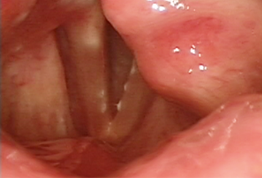

Vocal cord paralysis

성대에 갑작스럽게 찾아오는 마비증상

편측성 성대마비의 비율이 가장 높으며 쉰목소리,

이중음성, 강도감소 등의 증상이 나타납니다.

주요 발성 기관 중 하나인 성대의 움직임은 뇌신경 작용으로 나타나는데

이러한 신경들에 손상이 오면 성대마비가 발생합니다.

편측성 성대마비의

주 증상은 쉰 목소리

편측성 성대마비의 경우 주 증상은 쉰목소리 이며

가끔 음식물이 기도로 넘어가는 흡인증상이 발생하기도 합니다.